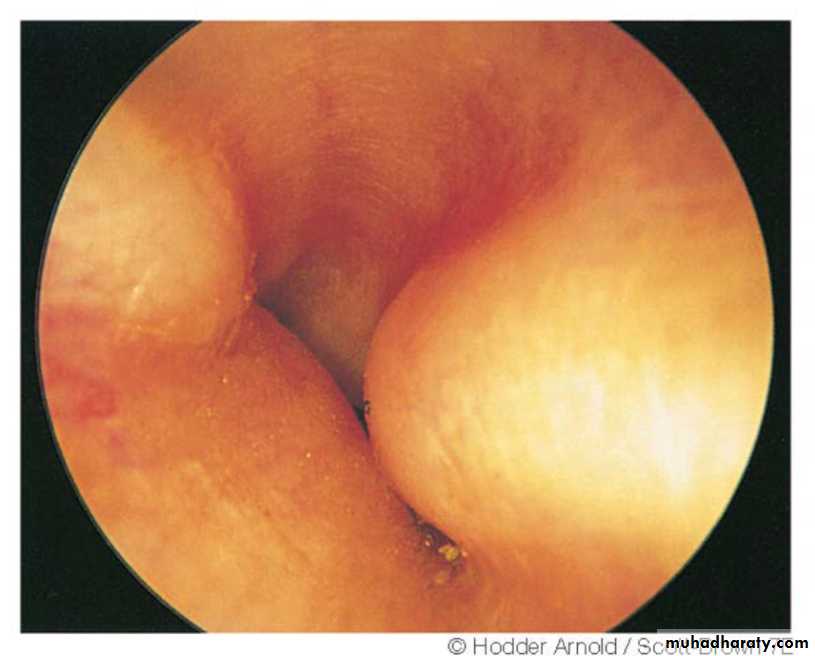

Exostoses

multiple and bilateral, presenting as smooth, sessile, bony swellings in the deeper part of the meatus near the TM. in persons exposed to entry of cold water in the meatus as in divers and swimmers. Males affected 3 times more than females. If small and asymptomatic, no treatment. If impair hearing or cause retention of wax and debris, may be removed with high speed drill.